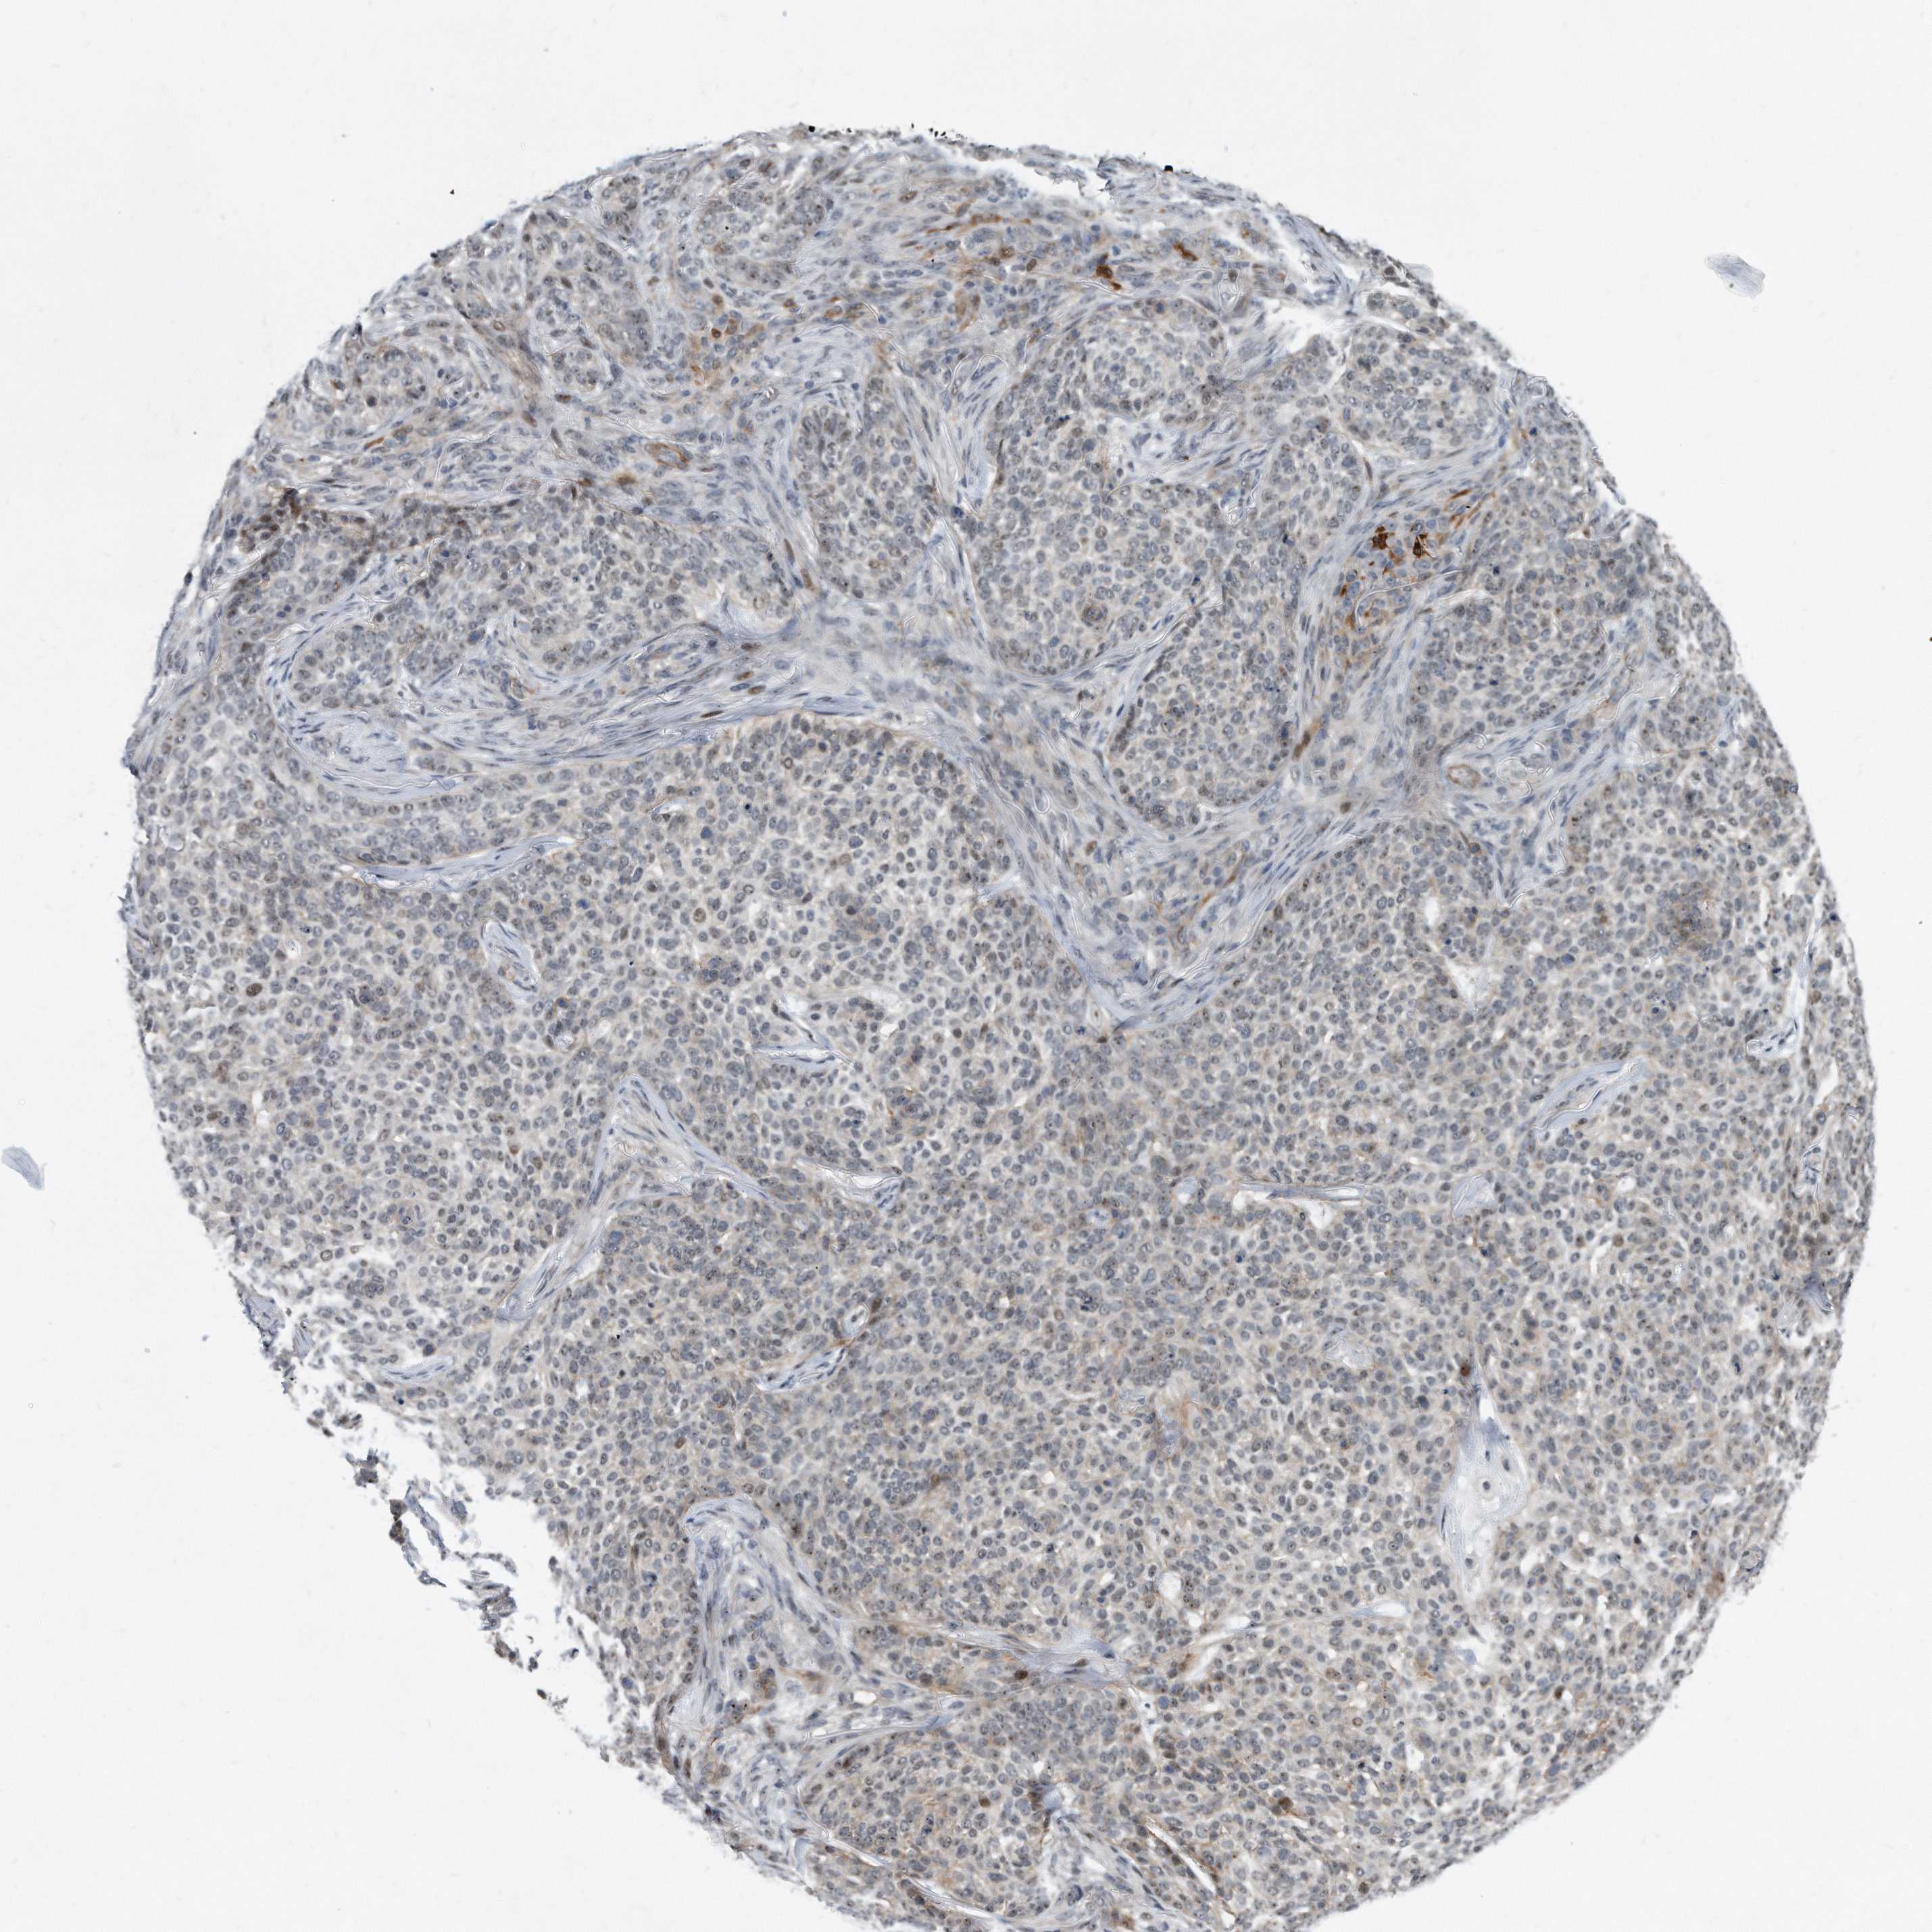

SKIN CANCER - Protein expressioni

A mouse-over function shows sample information and annotation data. Click on an image to view it in a full screen mode. Samples can be filtered based on level of antibody staining by selecting one or several of the following categories: high, medium, low and not detected. The assay and annotation is described here.

Antibody stainingi

Antibody staining in the annotated cell types in the current human tissue is reported as not detected, low, medium, or high, based on conventional immunohistochemistry profiling in selected tissues. This score is based on the combination of the staining intensity and fraction of stained cells.

Each image is clickable and will lead to virtual microscopy that enables deeper exploration of all samples and also displays staining intensity scores, fraction scores and subcellular localization as well as patient and tissue information for each sample.

Antibody HPA029888

Antibody HPA029889

Antibody HPA029890

Squamous cell carcinoma, NOS